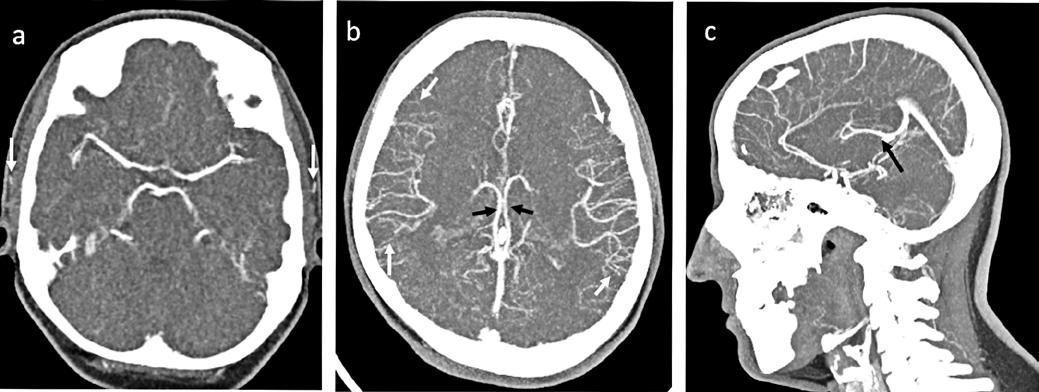

În cazul opacifierii unilaterale a uneia dintre cele două artere cerebrale medii, diagnosticul de MC poate fi afirmată dacă este absentă opacifierea venelor cerebrale interne (Fig,2).

Fig.